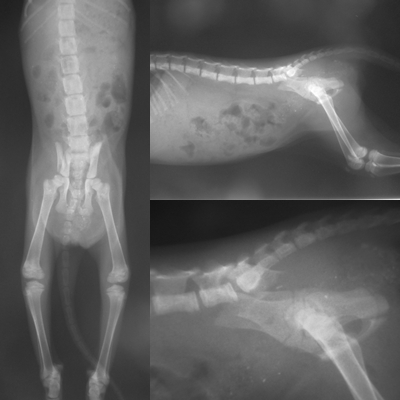

5/21送醫後…醫生表示小貓(0.52kg,體溫38.2度C) ,後軀無法站立,

骨盆左右腸骨骨折,及脊椎受傷,(雖有痛覺但本體反射差),

眼鼻有分泌物,有輕微鼻氣管炎的症狀,初步驗血結果為白血球過高(受傷發炎),

紅血球過低(貧血,有可能出血導致),肝指數亦有偏高(可能撞擊造成的傷害),

目前先輸液及藥物治療,待身體状況穩定後,再評估手術

小艾咪趕快養好身體,就可安排開刀事宜(骨盆左右腸骨骨折)……

關於骨盆左右腸骨骨折…除了樂生,我還去諮詢杜專科動物醫院

但長大後,可能會因此部位曾經骨折導致骨盆狹小而日後無法自行排便